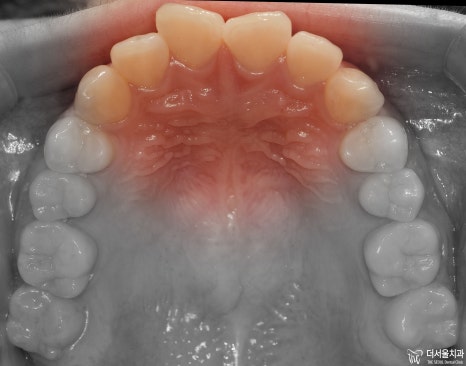

먼저 교합면에서 보게 되면, 앞니들의 총생이 관찰됩니다.

정면에서는 뭔가…. 그렇게 고르지 않은 치열이라는게 느껴지죠?

어색한 느낌이 계속 듭니다.